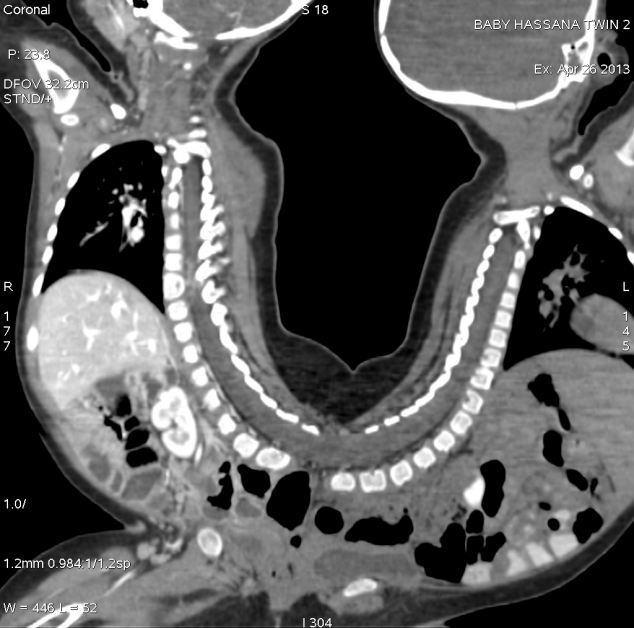

The twins, who were born with a condition called pygopagus had fused spines, shared a gastrointestinal passage and genitalia. The one year old twins were separated after a marathon operation on August 12.